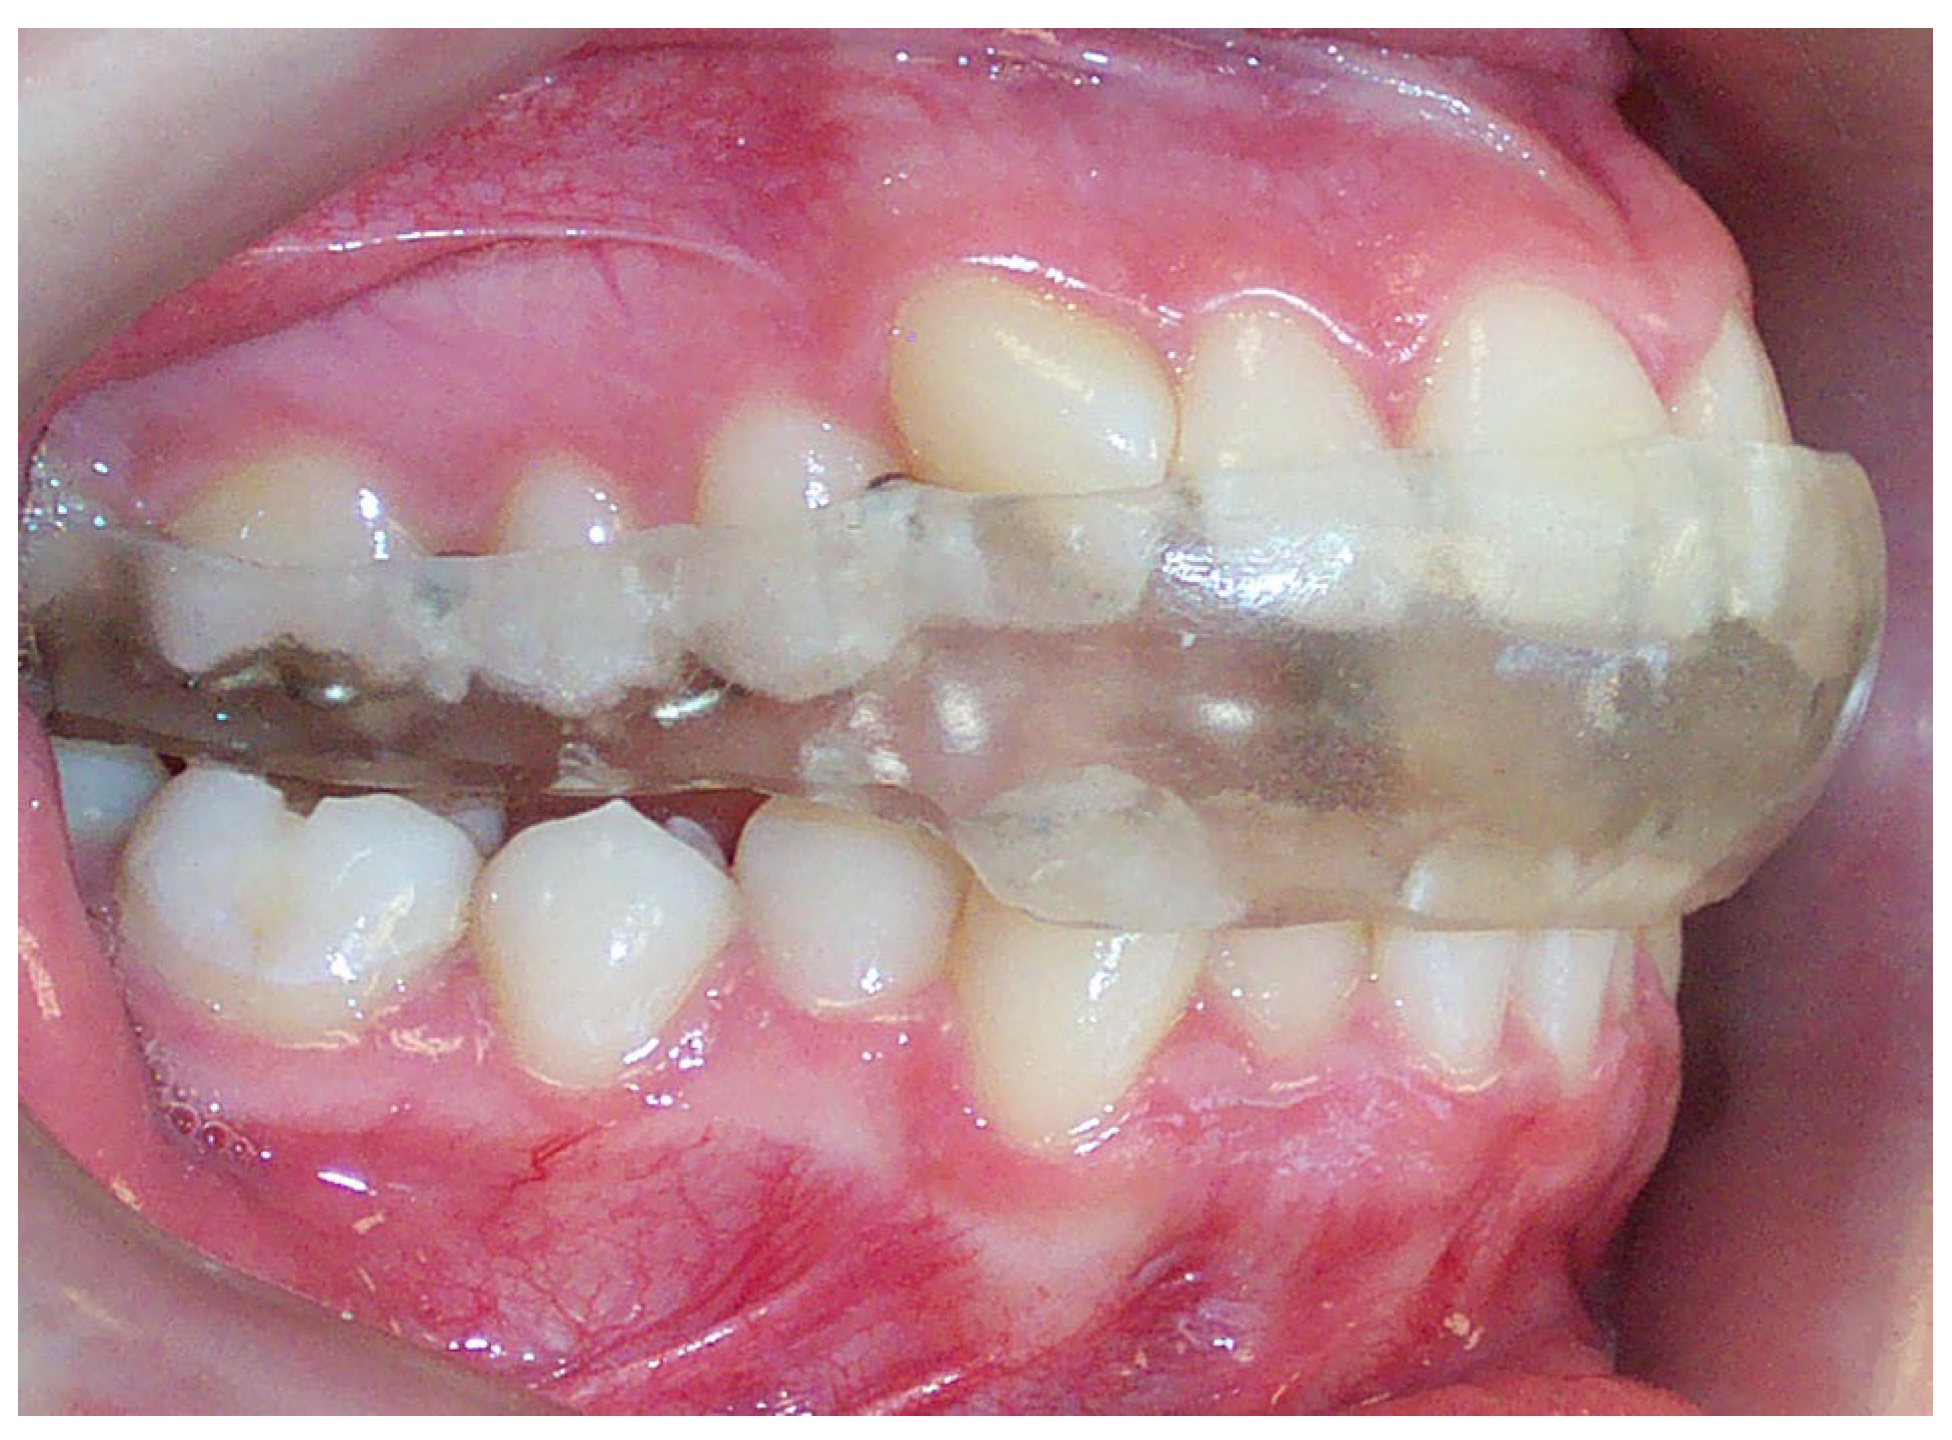

2. Materials and Methods

2.1. Subjects

2.2. Assessment of the Signs and Symptoms of TMD